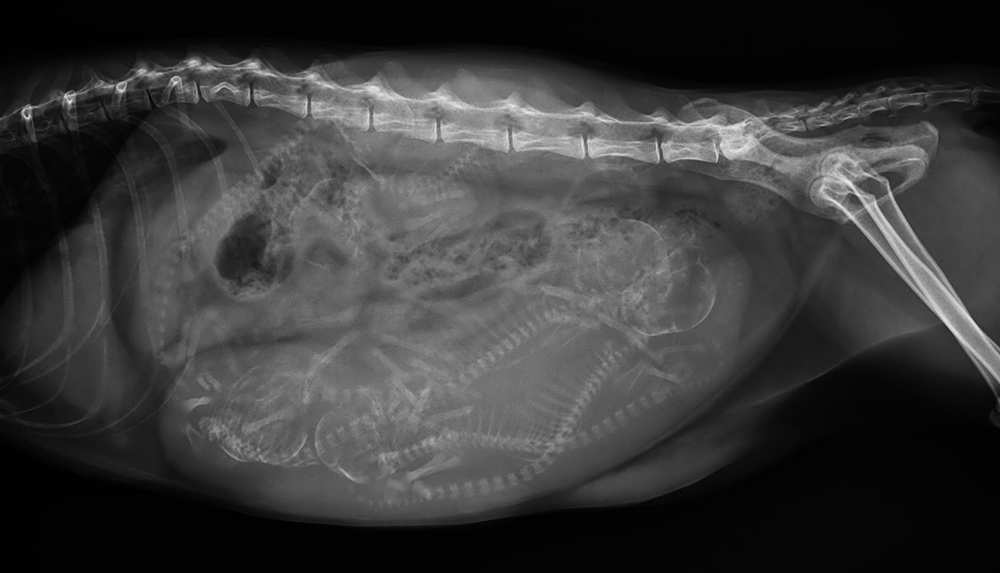

案例展示

Case List